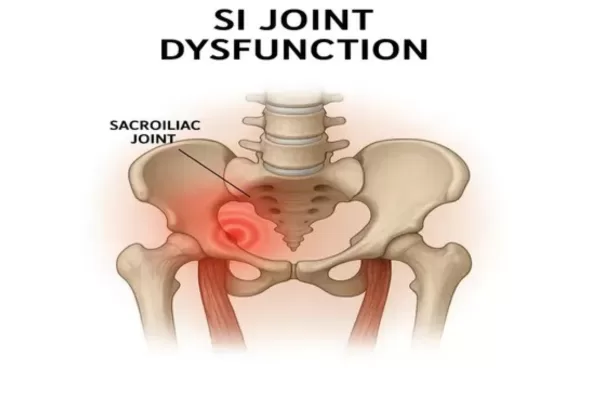

SI Joint Dysfunction Treatment

Hip or lower back stiffness? Your sacroiliac joints may be the culprit. Learn more about SI joint dysfunction. Read more